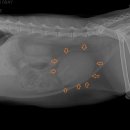

• 24시 에피소드 동물 메디컬 센터 | 만촌동 동물병원 강아지 요골·척골 골절 수술 후기 [24시에피소드동물메디컬센터]

만촌동 동물병원 강아지 요골·척골 골절 수술 후기 [24시에피소드동물메디컬센터] 만촌동 동물병원 ​ 안녕하세요. ​ 풍부한 경험과 따듯한 진료를 바탕으로, 반려동물의 건강하고 행복한 하루하루를 함께 만들어 가는 만촌동 동물병원 24시에피소드동물메디컬센터 입니다. 24시에피소드동물메디컬센터 대구광역시 동구...

에피소드동물메디컬센터(2025-06-26 12:41:00)